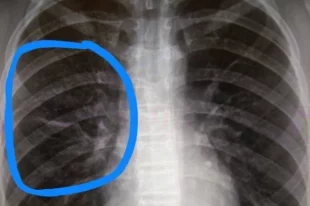

С начала года врачи выявили рак лёгких у 639 жителей Удмуртии

Чаще всего заболевание выявляется у мужчин.

Московские врачи диагностировали у мужчины центральный рак левого лёгкого III стадии, синхронный рак сигмовидной кишки III стадии и сопутствующая эпендимома.